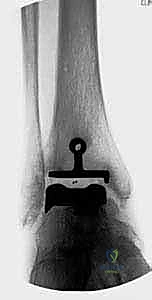

- الأشعة السينية (X-rays) بوضعية الوقوف: وهي الأداة الذهبية للتشخيص. صور الأشعة والوزن محمل على القدم (Weight-bearing X-rays) تظهر بدقة مدى تآكل الغضروف (ضيق المسافة المفصلية)، وجود نتوءات عظمية (Osteophytes)، وأي انحراف في المحور الميكانيكي للساق.

1. نظام سالتو لمفصل الكاحل الكلي (Salto Total Ankle Prosthesis - Mobile Bearing)

مفصل سالتو الأصلي هو ثمرة أبحاث أوروبية مكثفة. تم تطويره بين عامي 1994 و 1996، وبدأ استخدامه السريري بنجاح باهر في يناير 1997.

* التصميم الميكانيكي: يُعرف بأنه نظام ذو "مكون متحرك" (Mobile-bearing). يتكون من ثلاثة أجزاء رئيسية:

1. مكون معدني يثبت في أسفل عظمة الساق (Tibia).

2. مكون معدني يثبت في أعلى عظمة الكاحل (Talus).

3. قطعة بلاستيكية من البولي إيثيلين عالي الكثافة (Polyethylene insert): هذه القطعة ليست ثابتة، بل تنزلق بحرية بين المكونين المعدنيين.

* الميزة الكبرى: هذا التصميم يسمح بـ "التموضع الذاتي" (Self-alignment). أثناء الحركة، تتحرك القطعة البلاستيكية لتتكيف مع القوى الميكانيكية، مما يقلل من الضغط الواقع على واجهة التثبيت بين المعدن والعظم، ويحاكي حركة الكاحل المعقدة بشكل رائع.

* التثبيت: هو مفصل "غير إسمنتي". يتم تغطية الأسطح المعدنية الملامسة للعظم بطبقة مسامية من التيتانيوم وهيدروكسي أباتيت (Hydroxyapatite). هذه الطبقة تشجع العظم الطبيعي للمريض على النمو داخل مسام المفصل (Bone Ingrowth)، مما يوفر تثبيتاً بيولوجياً صلباً يدوم لسنوات طويلة.

2. نظام سالتو تالاريس (Salto-Talaris Prosthesis - Fixed Bearing)

بناءً على النجاح الهائل لنظام سالتو، تم تطوير نظام سالتو تالاريس لتلبية متطلبات مدارس جراحية مختلفة (خاصة في الولايات المتحدة).

* التصميم الميكانيكي: يشارك هذا النظام نفس الهندسة التشريحية الممتازة للمكونات المعدنية لنظام سالتو، ولكن مع اختلاف جوهري واحد: المكون البلاستيكي (البولي إيثيلين) هنا ثابت (Fixed-bearing) ويتم قفله بإحكام داخل المكون المعدني العلوي (الظنبوبي).

* الفلسفة وراء التصميم: أثبتت الأبحاث وخبرة الجراحين، بما في ذلك الأستاذ الدكتور محمد هطيف، أنه إذا تم إجراء القصات العظمية أثناء الجراحة بدقة متناهية تتوافق مع التشريح الطبيعي، فإن الحاجة إلى حركة واسعة للمكون البلاستيكي تقل بشكل كبير.

* الميزة الكبرى: نظام سالتو تالاريس يوفر استقراراً